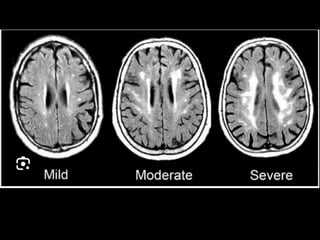

critérios  McDonald  (2017)   • disseminação  no  espaço   – RM  por  ≥  1  lesões  hiperintensas  em  T2,   sintomá+cas  ou  assintomá+cas,  que  são   caracterís+cos  de  EM,  em  dois  ou  mais  das   seguintes  quatro  áreas  do  sistema  nervoso   central:     • periventricular,     • cor+cal/justacor+cal,  infratentorial  e  medula  espinhal.

• disseminação  no  tempo   – presença  simultânea  de  lesões  captantes  de   gadolíneo  e  lesões  não  captantes  em  qualquer   exame  de  RM,     – ou  nova  lesão  hiperintensa  em  T2  ou  captante  de   gadolínio  quanto  comparada  a  um  exame  de  RM   prévio,  independentemente  do  momento  em  que   foi  realizado.

Diagnóstico:   Observação: ARM pode evidenciar áreas com pontos brilhantes indefinidos em indivíduos saudáveis; Gadolínio: • realçar lesões, • destacar se a doença está em estado ativo